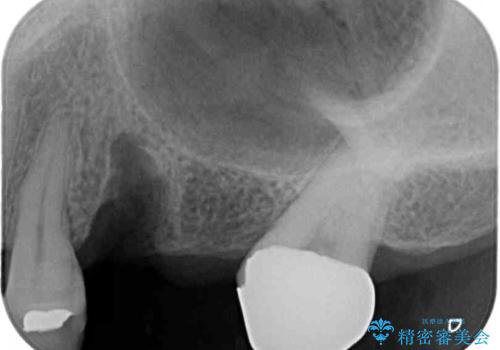

- 奥歯を他院で抜歯した後、インプラント治療を希望とのことで来院された患者様です。

ブリッジの支台を抜歯したことで2本のインプラントが必要であり、その後方はインプラント埋入に必要な骨量が不足していたため、上顎洞粘膜の挙上を行うこととしました。